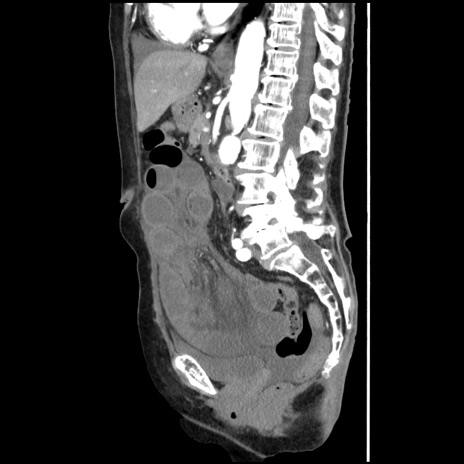

横断像

【症例】80歳代女性

【主訴】腹痛

【現病歴】8時間前から腹痛あり来院。

【既往歴】糖尿病、脂質異常症、子宮体癌にて子宮全摘術

【身体所見】意識清明・会話良好だが腹痛で苦悶様、全腹部にわたって反跳痛と圧痛あり

【データ】WBC 13600、CRP 0.14、LDH 224、CK 90